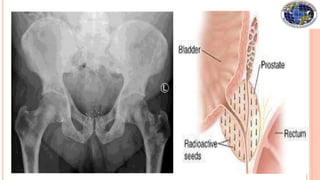

 Permanent- also known as seed implantation, involves placing

small LDR radioactive seeds or pellets (about the size of a grain of rice) in

the tumor or treatment site and leaving them there permanently to

gradually decay. Eg :- I125 ,Pd103, Au198

 Interstitial - the sources are placed directly in the target

tissue of the affected site, such as the prostate or breast.